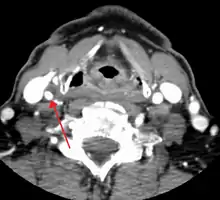

CT image of a 70 percent stenosis of the right internal carotid artery

Carotid artery stenosis is usually diagnosed by color flow duplex ultrasound scan of the carotid arteries in the neck. This involves no radiation, no needles and no contrast agents that may cause allergic reactions. This test has good sensitivity and specificity.[16]

Typically duplex ultrasound scan is the only investigation required for decision making in carotid stenosis as it is widely available and rapidly performed. However, further imaging can be required if the stenosis is not near the bifurcation of the carotid artery.[17]

One of several different imaging modalities, such as a computed tomography angiogram (CTA)[18][19][20] or magnetic resonance angiogram (MRA) may be useful. Each imaging modality has its advantages and disadvantages - Magnetic resonance angiography and CT angiography with contrast is contraindicated in patients with chronic kidney disease, catheter angiography has a 0.5% to 1.0% risk of stroke, MI, arterial injury or retroperitoneal bleeding. The investigation chosen will depend on the clinical question and the imaging expertise, experience and equipment available.[21]